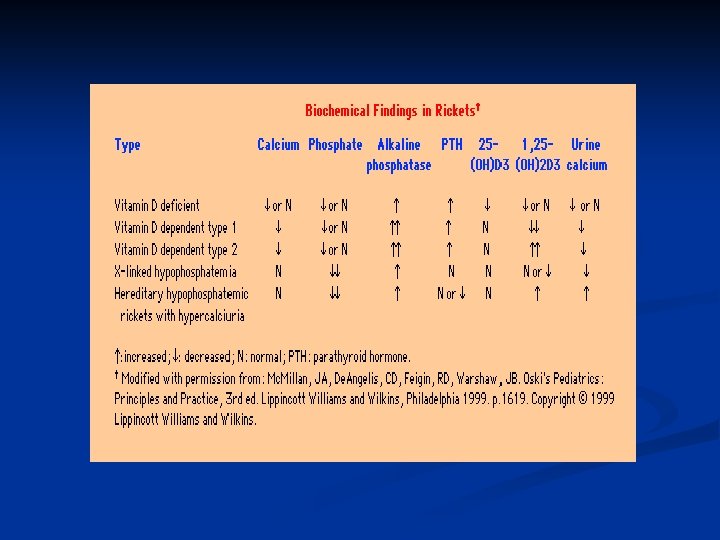

Biochemical findings in rickets n Alkaline phosphatase usually is ↑in all forms of rickets. n Serum phosphorus concentrations usually are↓ in both hypocalcemic and hypophosphatemic rickets. n Serum Ca is ↓only in hypocalcemic rickets. n Serum parathyroid hormone typically is ↑in hypocalcemic rickets, in contrast it is N in hypophosphatemic rickets. n 25 -OH vitamin D reflect the amount of vitamin D stored in the body, and is ↓in vit D deficiency. n 1, 25 -OH 2 vitamin D can be↓, N or ↑in hypocalcemic rickets and usually is N or slightly ↑in hypophosphatemic rickets.

Biochemical findings of rickets n Vitamin D deficiency rickets Low- normal serum calcium level n Increased secretion of PTH (secondary hyperparathyroidism) to compensate for low calcium n Hyperparathyroidism will increase renal excretion of phosphate, leads to low serum phosphate level n Elevated alkaline phosphatase enzyme n Reduced urinary calcium level n Low level of both 25 and 1, 25 - di hydroxy n

Biochemical findings of rickets Hypophosphatemic rickets n Low serum phosphate level n Normal calcium level n Normal parathyroid hormone level n High alkaline phosphatase level n In-appropriate low or normal 1, 25 -di hydroxy vitamin D n phosphate is the major stimulus for 1 hydroxylase